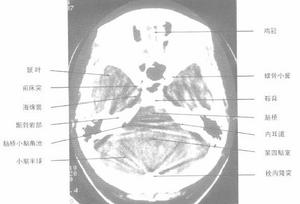

側顱底解剖圖側顱底指以鼻咽頂壁中心,向前外經翼齶窩達眶下裂前端,向後外經頸靜脈窩到乳突後緣兩條假想線之間的三角區。側顱底區常見的腫瘤有鼻咽癌、中耳癌、中神經與面神經鞘膜瘤、腦膜瘤、畸胎瘤、先天性膽脂瘤等;其中重要而複雜者為頸靜脈球體瘤。頸靜脈球體瘤又稱血管球瘤。

顱底劃分,尚未統一,所謂側顱底指以鼻咽頂壁中心,向前外經翼齶窩達眶下裂前端,向後外經頸靜脈窩到乳突後緣兩條假想線之間的三角區,該區包括頸內動脈孔、頸靜脈孔、卵圓孔,棘孔、莖乳孔和由各孔穿行的腦神經和血管,另外還有顳頜關節,咽鼓管骨部等,側顱底區常見的腫瘤有鼻咽癌,中耳癌、聽神經與面神經鞘膜瘤,腦膜瘤、畸胎瘤、先天性膽脂瘤等,其中重要而複雜者為頸靜脈球體瘤。頸靜脈球體瘤又稱血管球瘤,是一種多發於中年以上婦女的良性中流,有家族發病傾向。

側顱底詳細圖解主要術後問題及處理原則